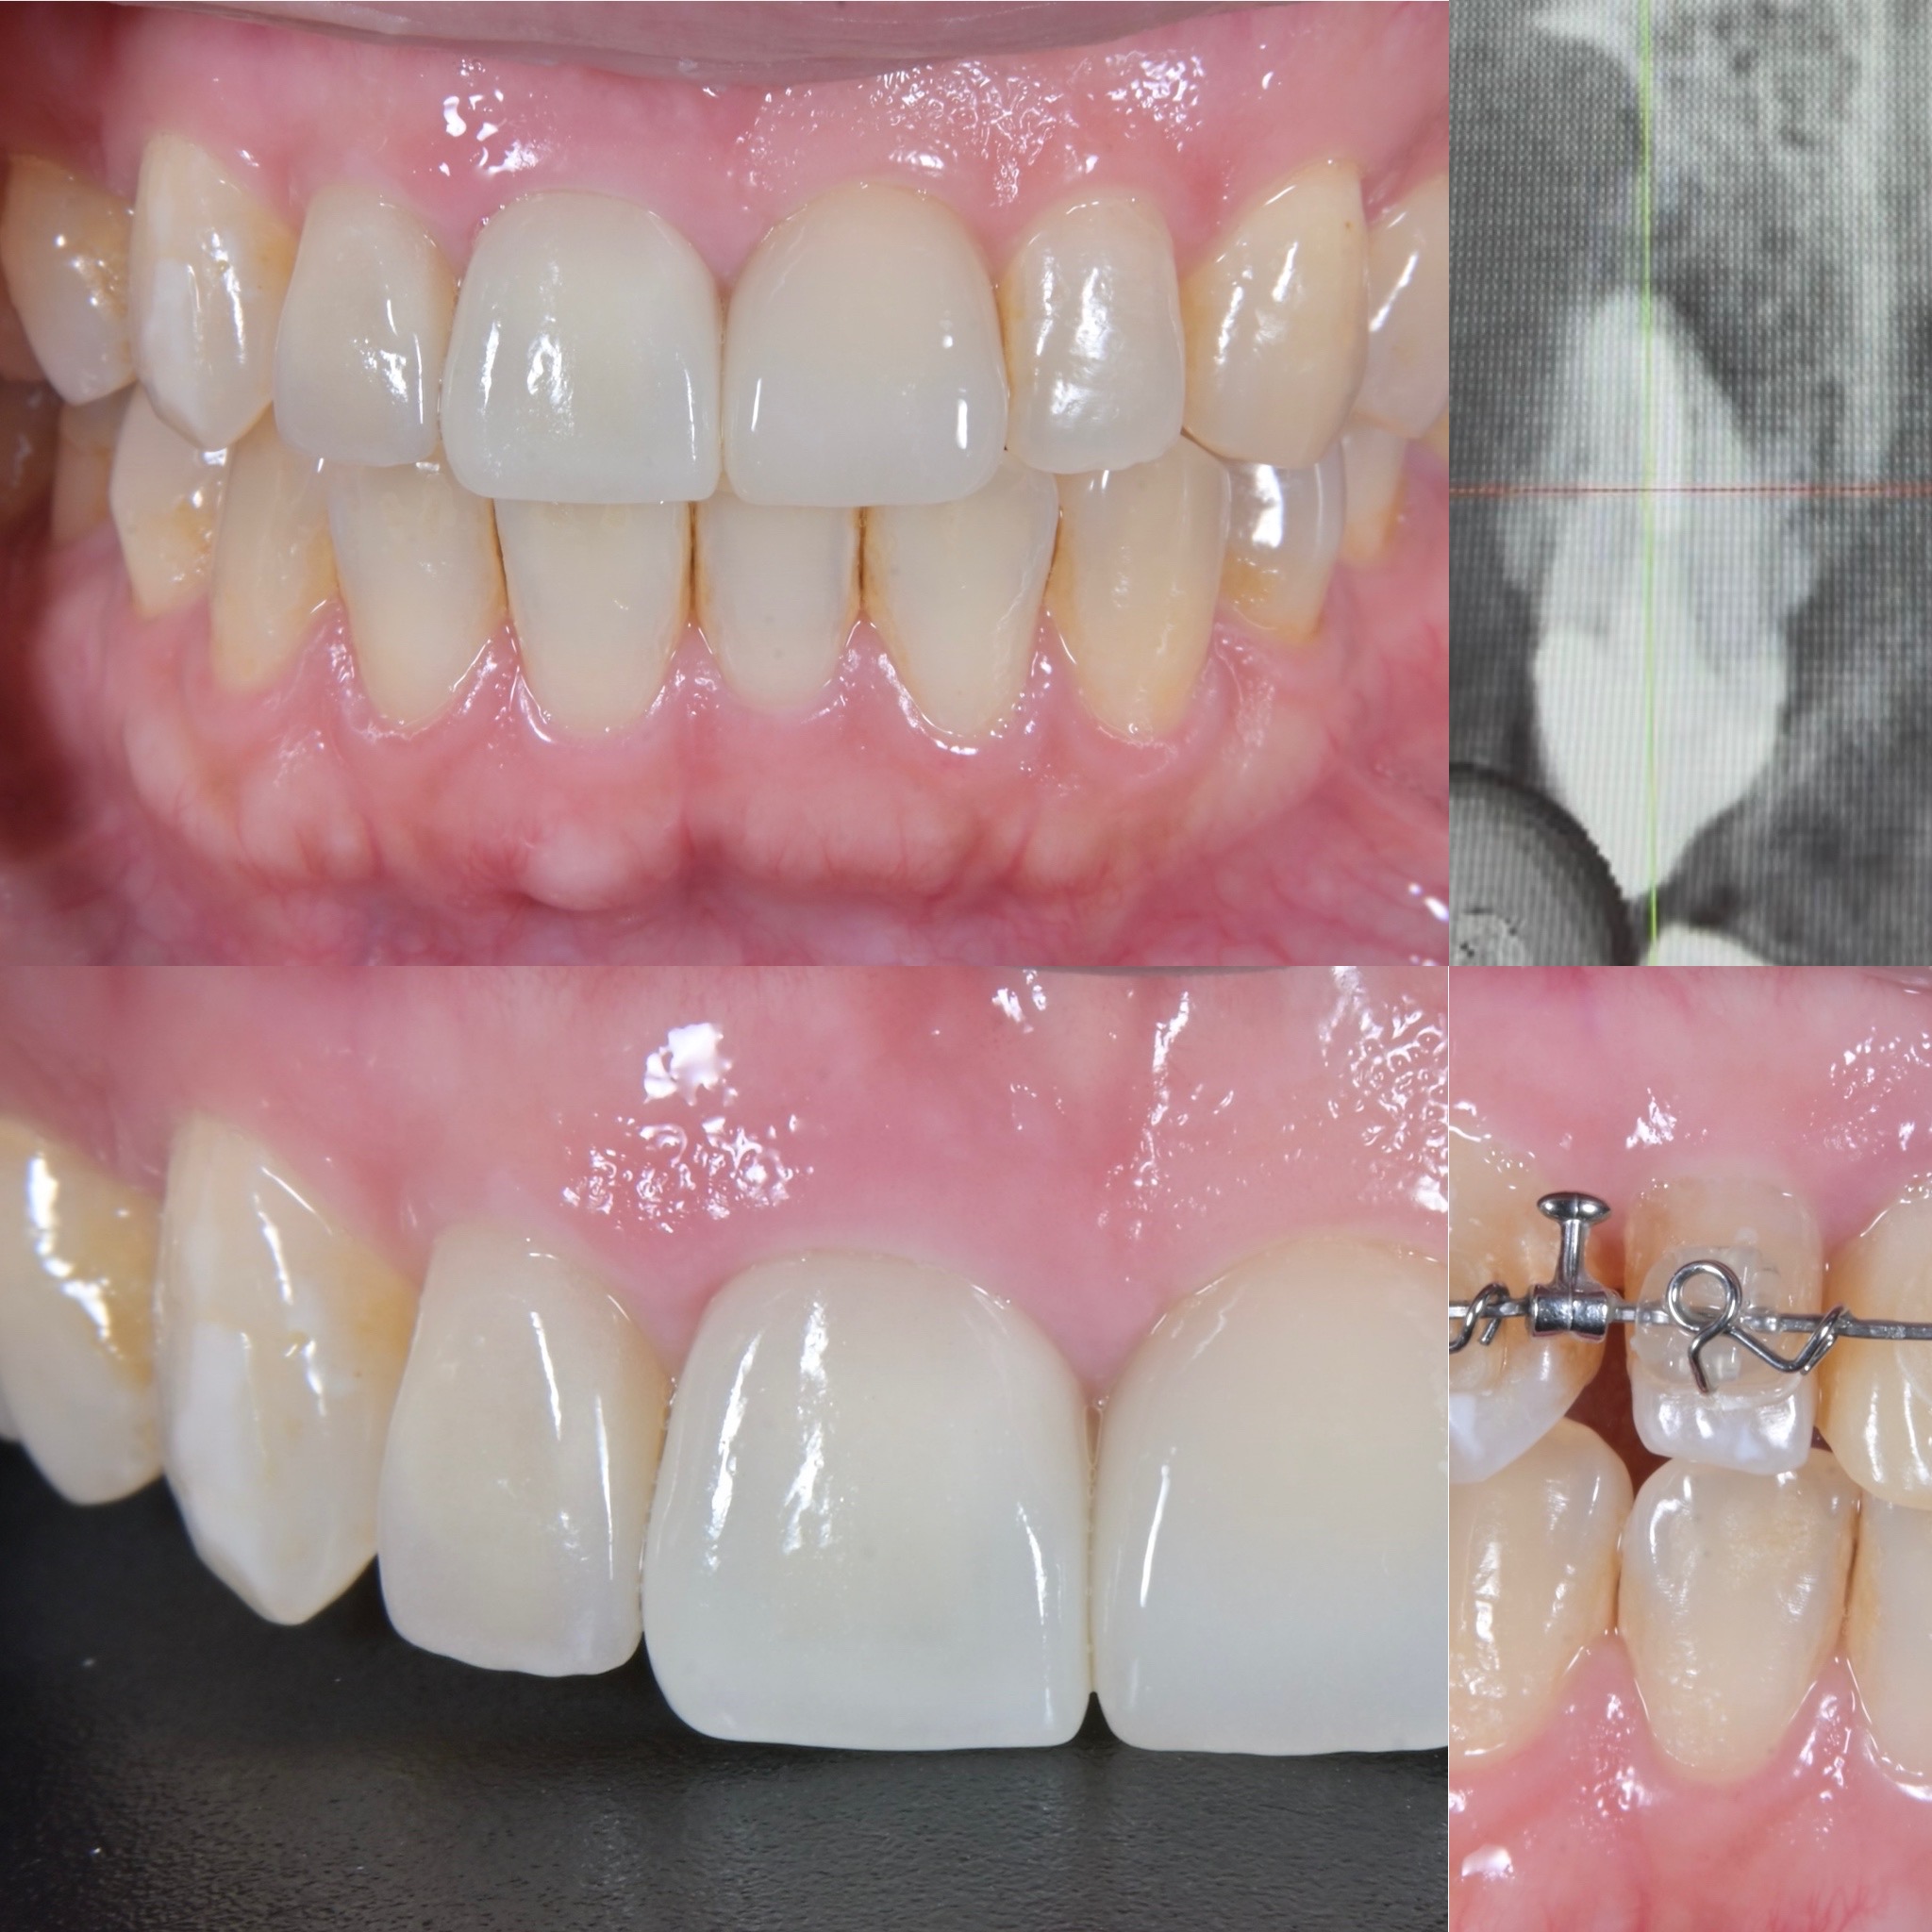

部分矯正(MTM)を併用した前歯部審美歯科治療

- 主訴

- 治療中の前歯の歯ぐきの腫れが治らないことを主訴に来院されました。

- 治療内容

- 右上前歯(中切歯)の根尖部に大きな病変と歯肉の腫脹を認めたため、専門医による根管治療(歯内療法:歯の神経の治療)後、歯を悪くしている要因の一つである咬み合わせの改善のため部分矯正を行い、ジルコニアクラウンにて歯冠修復を行いました。矮小歯の側切歯はラミネートベニアにて修復治療を行なっています。

- 治療期間

- 矯正期間16ヶ月

- 治療費用

- ジルコニアクラウン 165,000円 ラミネートベニア 143,000円 部分矯正 440,000円

- 治療のリスク

- 大変大きな病変と歯牙の動揺があり、保存が危ぶまれましたが、確実な感染防護と手技により抜歯を免れました。このままのかみ合わせ(シザーズバイト・交叉咬合)では再発リスクがあるため、矯正治療を行うことでアンテリアガイダンスを獲得、スムーズな離開運動を達成することができた。矮小歯の側切歯にはラミネートベニア、主訴の中切歯にはジルコニアクラウンで修復することで審美性も獲得することができました。矯正治療後に保定装置を怠ると後戻りすることがありますので定期的な検診が必要です。

BEFORE

AFTER